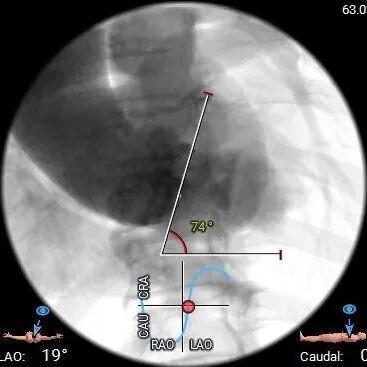

•主动脉瓣水平夹角约74°,严重横位心,主动脉弓宽度角度可,弓顶部有钙化分布,

•推荐18mm球囊预扩,预装AV29瓣膜。

手术影像记录